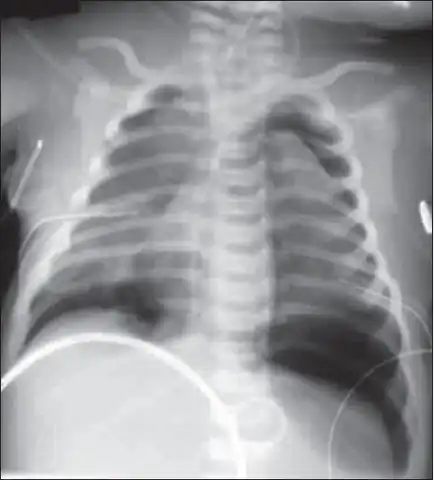

Bilateral pneumothorax seen in a newborn with meconium aspiration

Release of meconium into the amniotic cavity and then intrauterine gasping of post-term neonates may cause meconium aspiration syndrome.